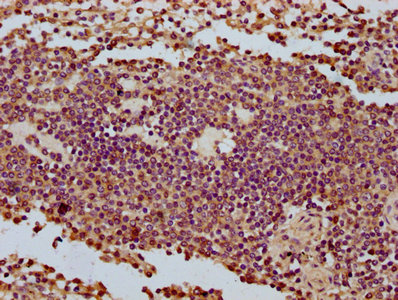

IHC image of CSB-PA896698LA01HU diluted at 1:500 and staining in paraffin-embedded human spleen tissue performed on a Leica BondTM system. After dewaxing and hydration, antigen retrieval was mediated by high pressure in a citrate buffer (pH 6.0). Section was blocked with 10% normal goat serum 30min at RT. Then primary antibody (1% BSA) was incubated at 4°C overnight. The primary is detected by a biotinylated secondary antibody and visualized using an HRP conjugated SP system.

IHC image of CSB-PA896698LA01HU diluted at 1:500 and staining in paraffin-embedded human liver cancer performed on a Leica BondTM system. After dewaxing and hydration, antigen retrieval was mediated by high pressure in a citrate buffer (pH 6.0). Section was blocked with 10% normal goat serum 30min at RT. Then primary antibody (1% BSA) was incubated at 4°C overnight. The primary is detected by a biotinylated secondary antibody and visualized using an HRP conjugated SP system.